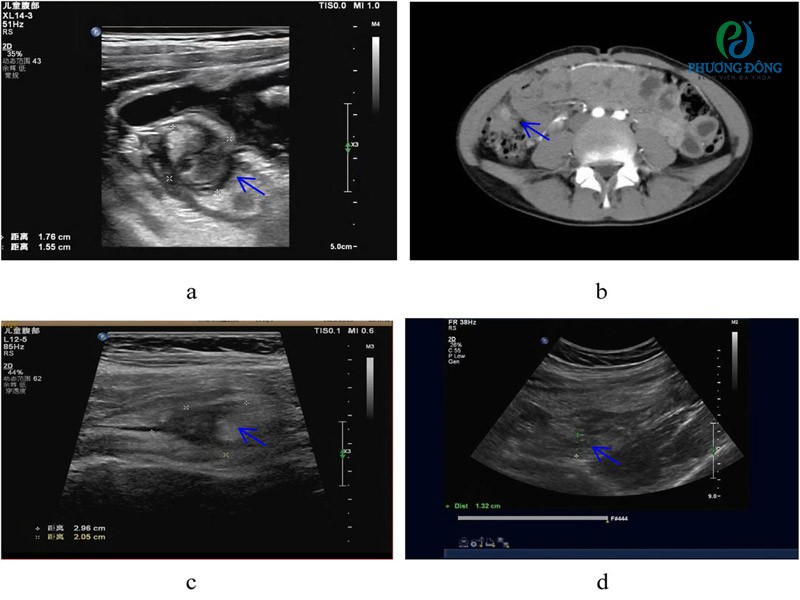

Hình ảnh siêu âm ổ bụng của bệnh nhân bị viêm túi thừa manh tràng

Ghi chú:

- (a, b) Ở trẻ em bị viêm túi thừa manh tràng đơn thuần, khối viêm có thể được nhìn thấy dưới siêu âm và CT (→ dấu).

- (c, d) Ở trẻ em bị viêm túi thừa manh tràng phức tạp, siêu âm chẩn đoán nhầm là viêm ruột thừa cấp.

Siêu âm ổ bụng: Có thể phát hiện hình ảnh thành ruột dày bất thường hoặc túi thừa đang viêm, tuy nhiên độ chính xác còn hạn chế.

Chụp CT scan ổ bụng: Đây là phương pháp được đánh giá có độ nhạy và độ đặc hiệu cao nhất, giúp xác định vị trí viêm, mức độ tổn thương, đồng thời loại trừ các bệnh lý có triệu chứng tương tự như viêm ruột thừa, viêm ruột Crohn, áp xe hoặc khối u.